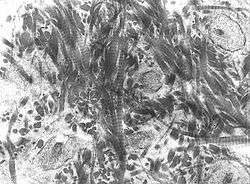

![]() A scanning electronic micrograph of bone at 10,000x magnification. | |